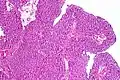

Transitional cell carcinoma, being low-grade to the left, and high-grade to the right. H&E stain -

Papillary transitional cell carcinoma, low grade -

Histopathology of urothelial carcinoma of the urinary bladder, showing a nested pattern of invasion. Transurethral biopsy. H&E stain -

Histopathology of urothelial carcinoma of the urinary bladder. -

Micrograph of urethral urothelial cell carcinoma. H&E stain